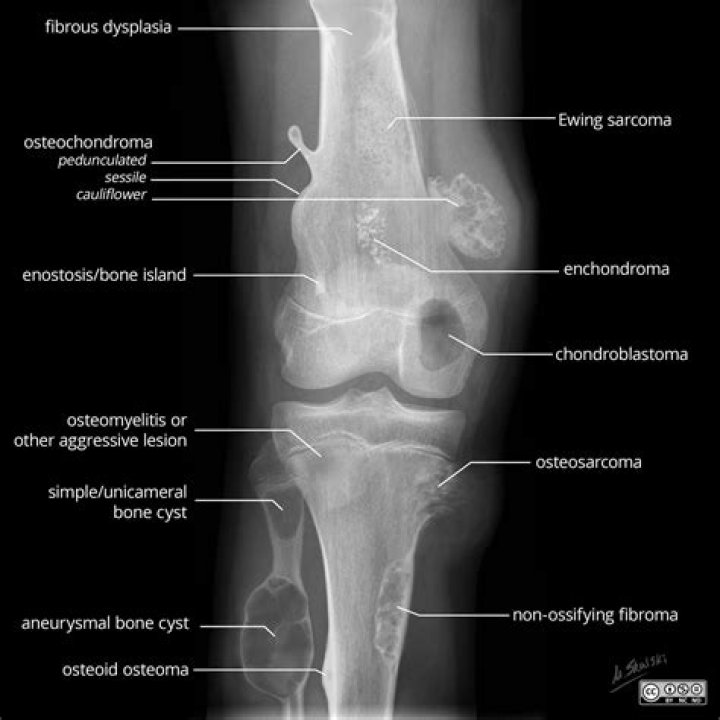

What does osteochondroma look like?

An osteochondroma looks like a bony projection on the external surface of a bone, like a bony mushroom on a stalk, usually near a growth plate area. It can occur in any bone but is seen most often around the knee or upper arm. This tumor generally grows with the child and stops growing once the child completes puberty.

Osteochondroma is an overgrowth of cartilage and bone that happens at the end of the bone near the growth plate. Most often, it affects the long bones in the leg, the pelvis, or the shoulder blade. Osteochondroma is the most common noncancerous bone growth.

What is an osseous excrescence?

An osteochondroma is a cartilage-covered bony excrescence (exostosis) that arises from the surface of a bone. Osteochondromas, which are the most common bone tumors in children, may be solitary or multiple, and they may arise spontaneously or as a result of previous osseous trauma.